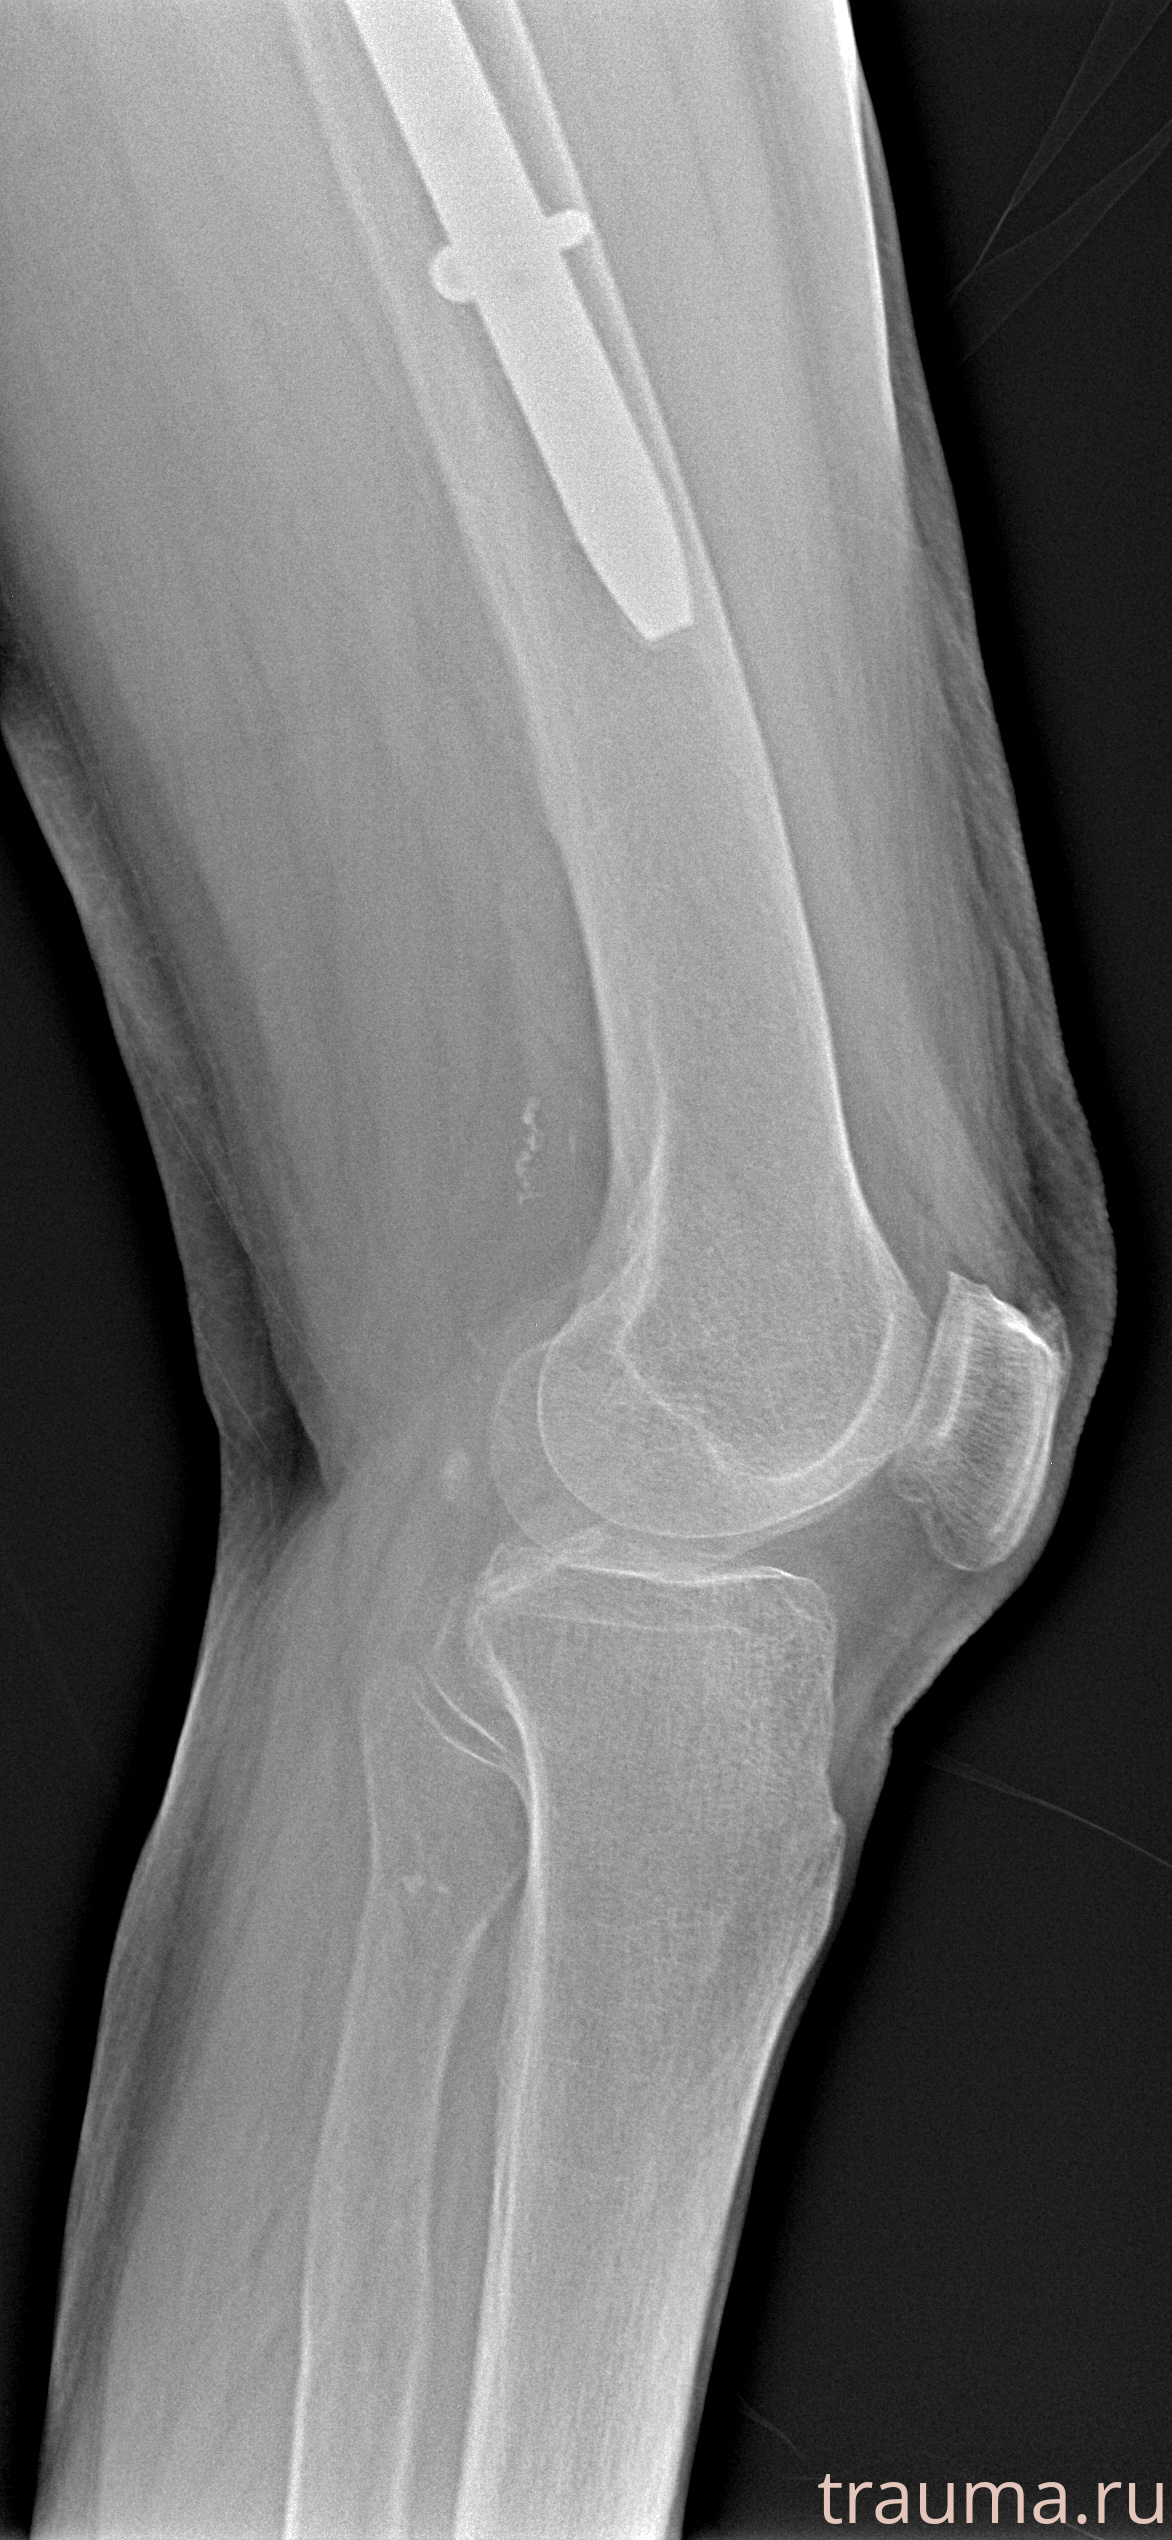

Рентгенограммы